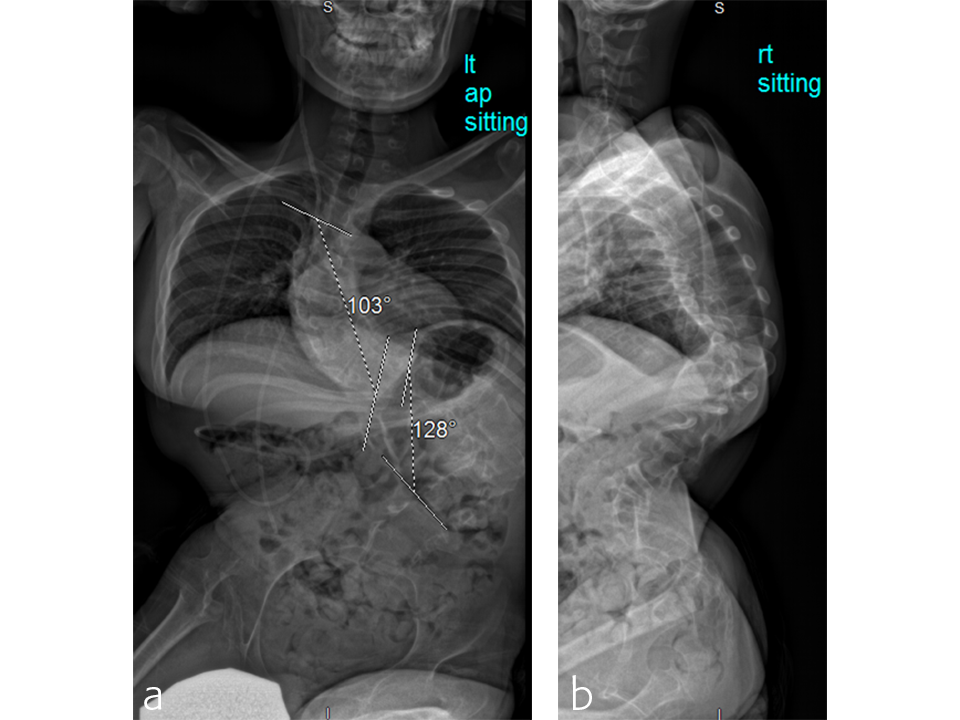

A T2 to pelvis, two-level vertebral column resection (VCR) was completed at the McGill University Health Center in 7 hours (Figs 5–7).